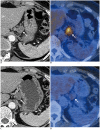

Tumor response may be assessed readily by the use of Response Evaluation Criteria in Solid Tumor version 1.1. However, the criteria mainly depend on tumor size changes. These criteria do not reflect other morphologic (tumor necrosis, hemorrhage, and cavitation), functional, or metabolic changes that may occur with targeted chemotherapy or even with conventional chemotherapy. The state-of-the-art multidetector CT is still playing an important role, by showing high-quality, high-resolution images that are appropriate enough to measure tumor size and its changes. Additional imaging biomarker devices such as dual energy CT, positron emission tomography, MRI including diffusion-weighted MRI shall be more frequently used for tumor response evaluation, because they provide detailed anatomic, and functional or metabolic change information during tumor treatment, particularly during targeted chemotherapy. This review elucidates morphologic and functional or metabolic approaches, and new concepts in the evaluation of tumor response in the era of personalized medicine (targeted chemotherapy).